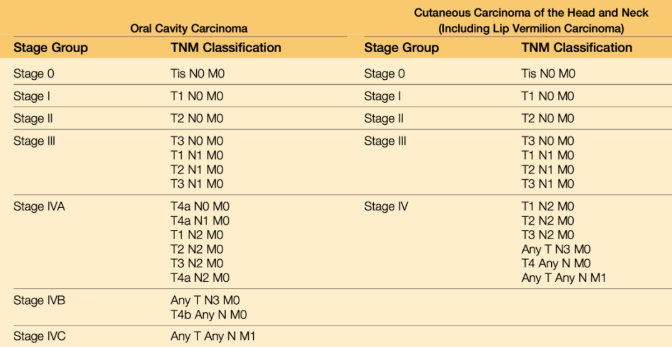

TNM staging

- Tumor: 原發性腫瘤(primary tumor)的大小和侵犯範圍

- 大小(cm)

- 深度 (DOI,mm)

TX: 無法評估Tis: carcinoma in situ

- Lymph Node: 擴散至區域淋巴結的程度

- 轉移的淋巴結顆數、大小(cm)、同/對/雙側(ipsi-, contra-, bi-)

- extranodal extension (ENE,淋巴結外擴散)

Minor: 擴散< 2 mmMajor: 擴散> 2 mmNX: 淋巴結無法被評估

- distant Metastasis?

M1:M0

Note

Oral melanoma staging

- T3: 黏膜

- T4a: 深軟組織、軟骨、硬骨、overlying skin

- T4b: 腦組織及腦神經、masticator space、頸動脈、prevertebral space、縱隔腔結構

OSCC and HPV- OPSCC staging

- T

| DOI(mm) \ size(cm) | < 2 | 2~4 | > 4 |

|---|---|---|---|

| < 5 | T1 | T2 | T3 |

| 5~10 | T2 | T2 | T3 |

| >10 | ? | T3 | T3 |

- N

| N | 淋巴結 | 大小 | ENE | |

|---|---|---|---|---|

| 1 | 單 | 同 | ≤ 3 cm | ✗ |

| 2a | 3-6 cm | |||

| 2b | 多 | ≤ 6cm | ||

| 2c | - | 對/雙 | ||

| 3a | - | - | > 6 cm | |

| 3b | - | - | - | ✓ |

- Staging